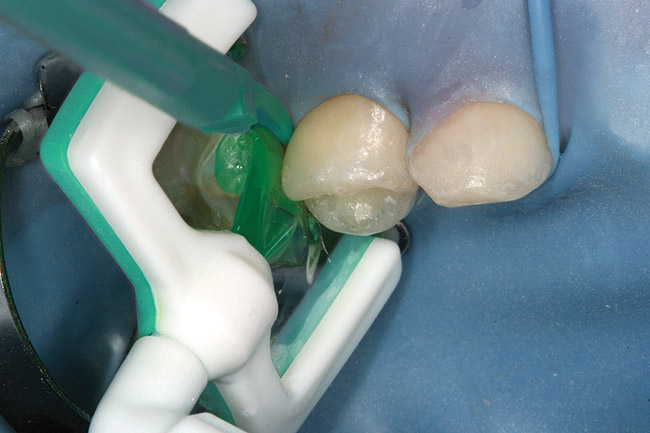

Caries infiltration is a simple, straightforward technique. Before treatment, the tooth should be thoroughly cleaned and isolated with a rubber dam (Figure 5 and Figure 6). Treatment kits contain all of the materials required for the technique (except the rubber dam), including specially designed proximal tips that are used for accurate delivery of the acid etch and infiltrant resin during the procedure. These carriers consist of an ultrathin film perforated on one side for direct placement at the treatment site, which protects adjacent teeth. The tips swivel 360°, allowing application from different angles. All syringes contained in the kit are screw-type applicators, which ensure controlled extrusion of the materials.

Specially designed dental wedges are inserted to slightly separate the carious tooth from adjacent teeth. A 15% hydrochloric gel is used to remove the "pseudointact" surface and open the pore system of the incipient lesion body (Figure 7).85 After rinsing (Figure 8), the area is dried with ethanol (Figure 9), followed by dry air. Then, the infiltrant is applied and allowed to penetrate the lesion pores by capillary action for 3 minutes (Figure 10). Any excess material is removed with dental floss, and the infiltrant is light cured from three angles for 40 seconds (Figure 11). A second layer of infiltrant is applied for 1 minute, and light cured for 40 seconds (Figure 12).86 It should be noted that the infiltrant is not radiopaque because fillers would affect the viscosity. Efficacy of the treatment can be tracked at future visits by lack of lesion progression.

Figure 6  Rubber dam and wedge in place.

Figure 6

Figure 7  Matrix in place showing extrusion of hydrochloric acid.

Figure 7

Figure 8  Rinsing of hydrochloric acid after removal of matrix.

Figure 8

Figure 9  Placement of needle tip to allow 1-minute treatment with alcohol dessicant.

Figure 9

Figure 10  Icon Infiltrant flowing through matrix channel into contact area on mesial of tooth A.

Figure 10

Figure 11  Light curing of infiltrant material.

Figure 11

Figure 12  Final view showing treated surface of mesial of tooth A.

Figure 12